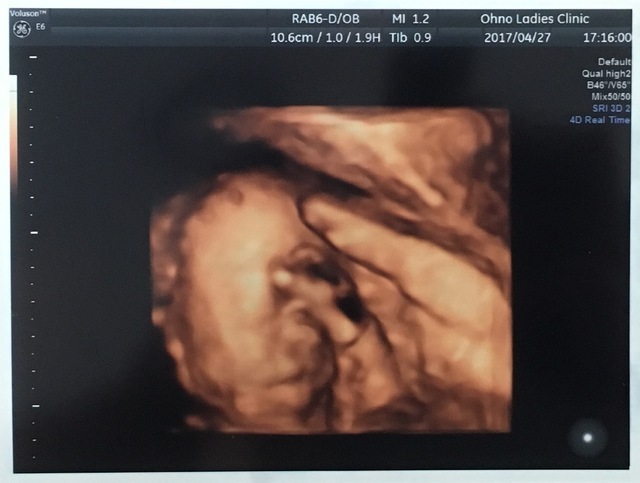

25週0日(25w0d・男の子)|まぁりん さん(31歳)

エコー写真撮影時のエピソード:

初めて顔の様子がハッキリわかった4Dエコーです!それまでなかなか4Dエコーをしてもらえず、ずっと顔が見たいと思っていました。里帰り先の産婦人科で撮っていただいたものです。旦那もこのエコー写真を見てとても喜んでいました。

私は4回の流産を経てやっとここまできたので、エコー写真をもらうたびにうれしくてたまりません!これからも大切に育てていきます。大きくなぁれ!